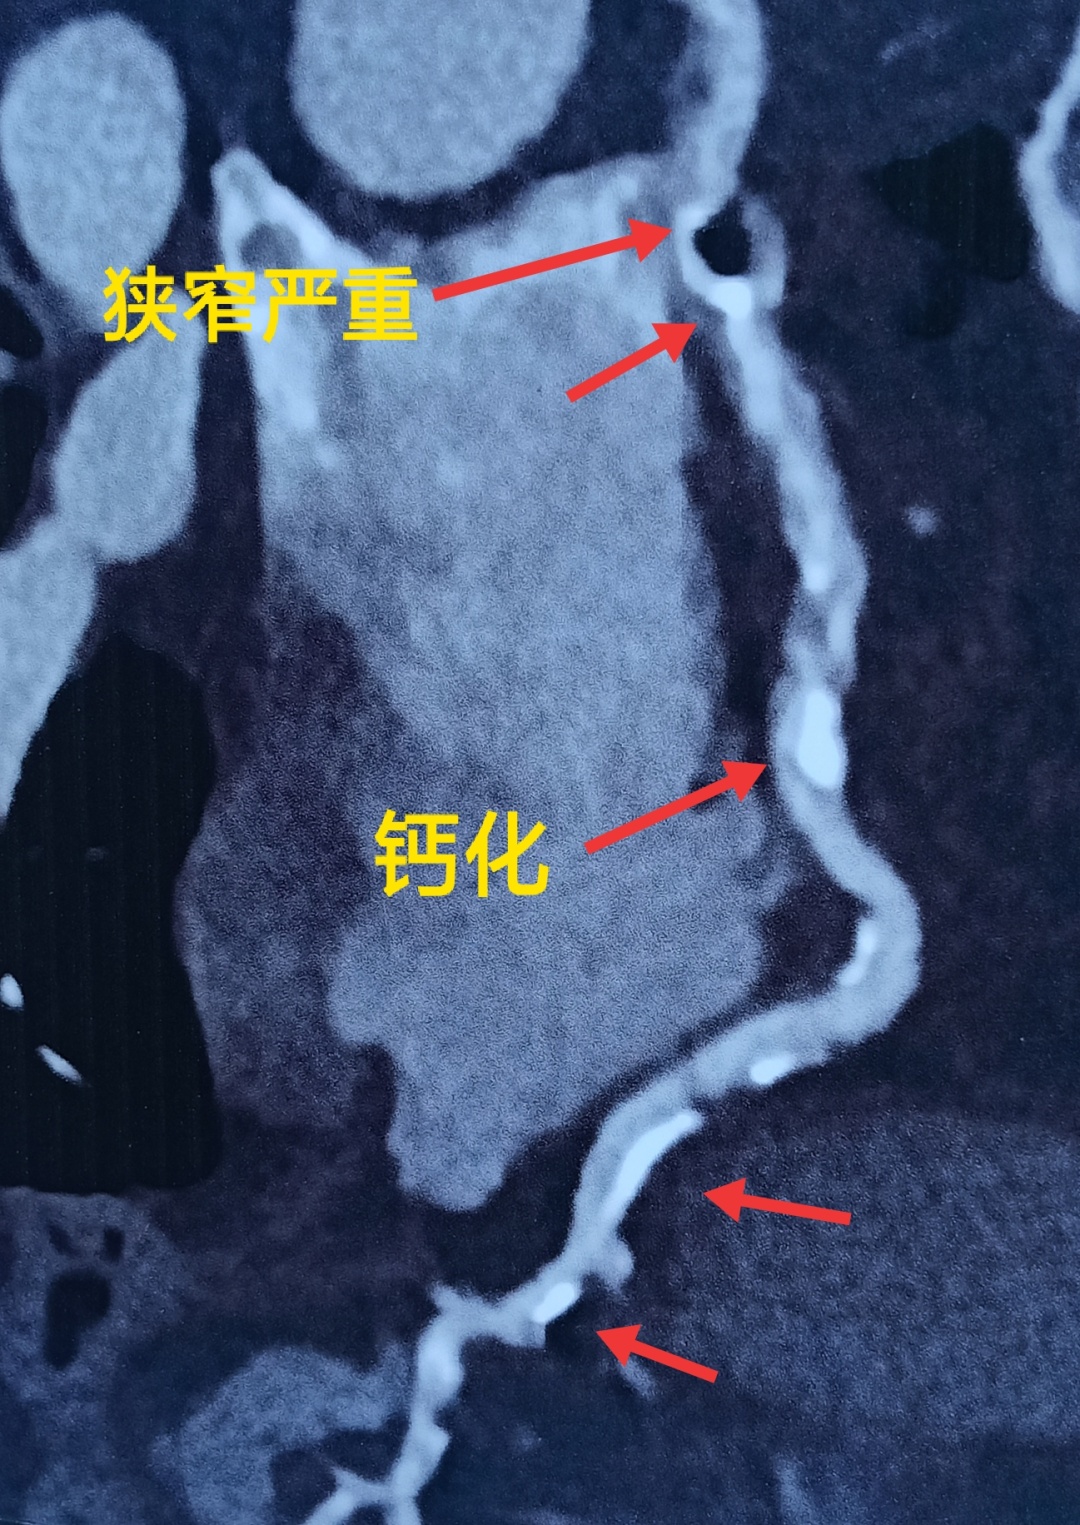

拿来她拍的CT片子,心脏前降支的钙化触目惊心。

前降支是给心脏供血的重要血管,这么多的钙化加上局部严重的狭窄,她的疼痛高度怀疑是心绞痛。